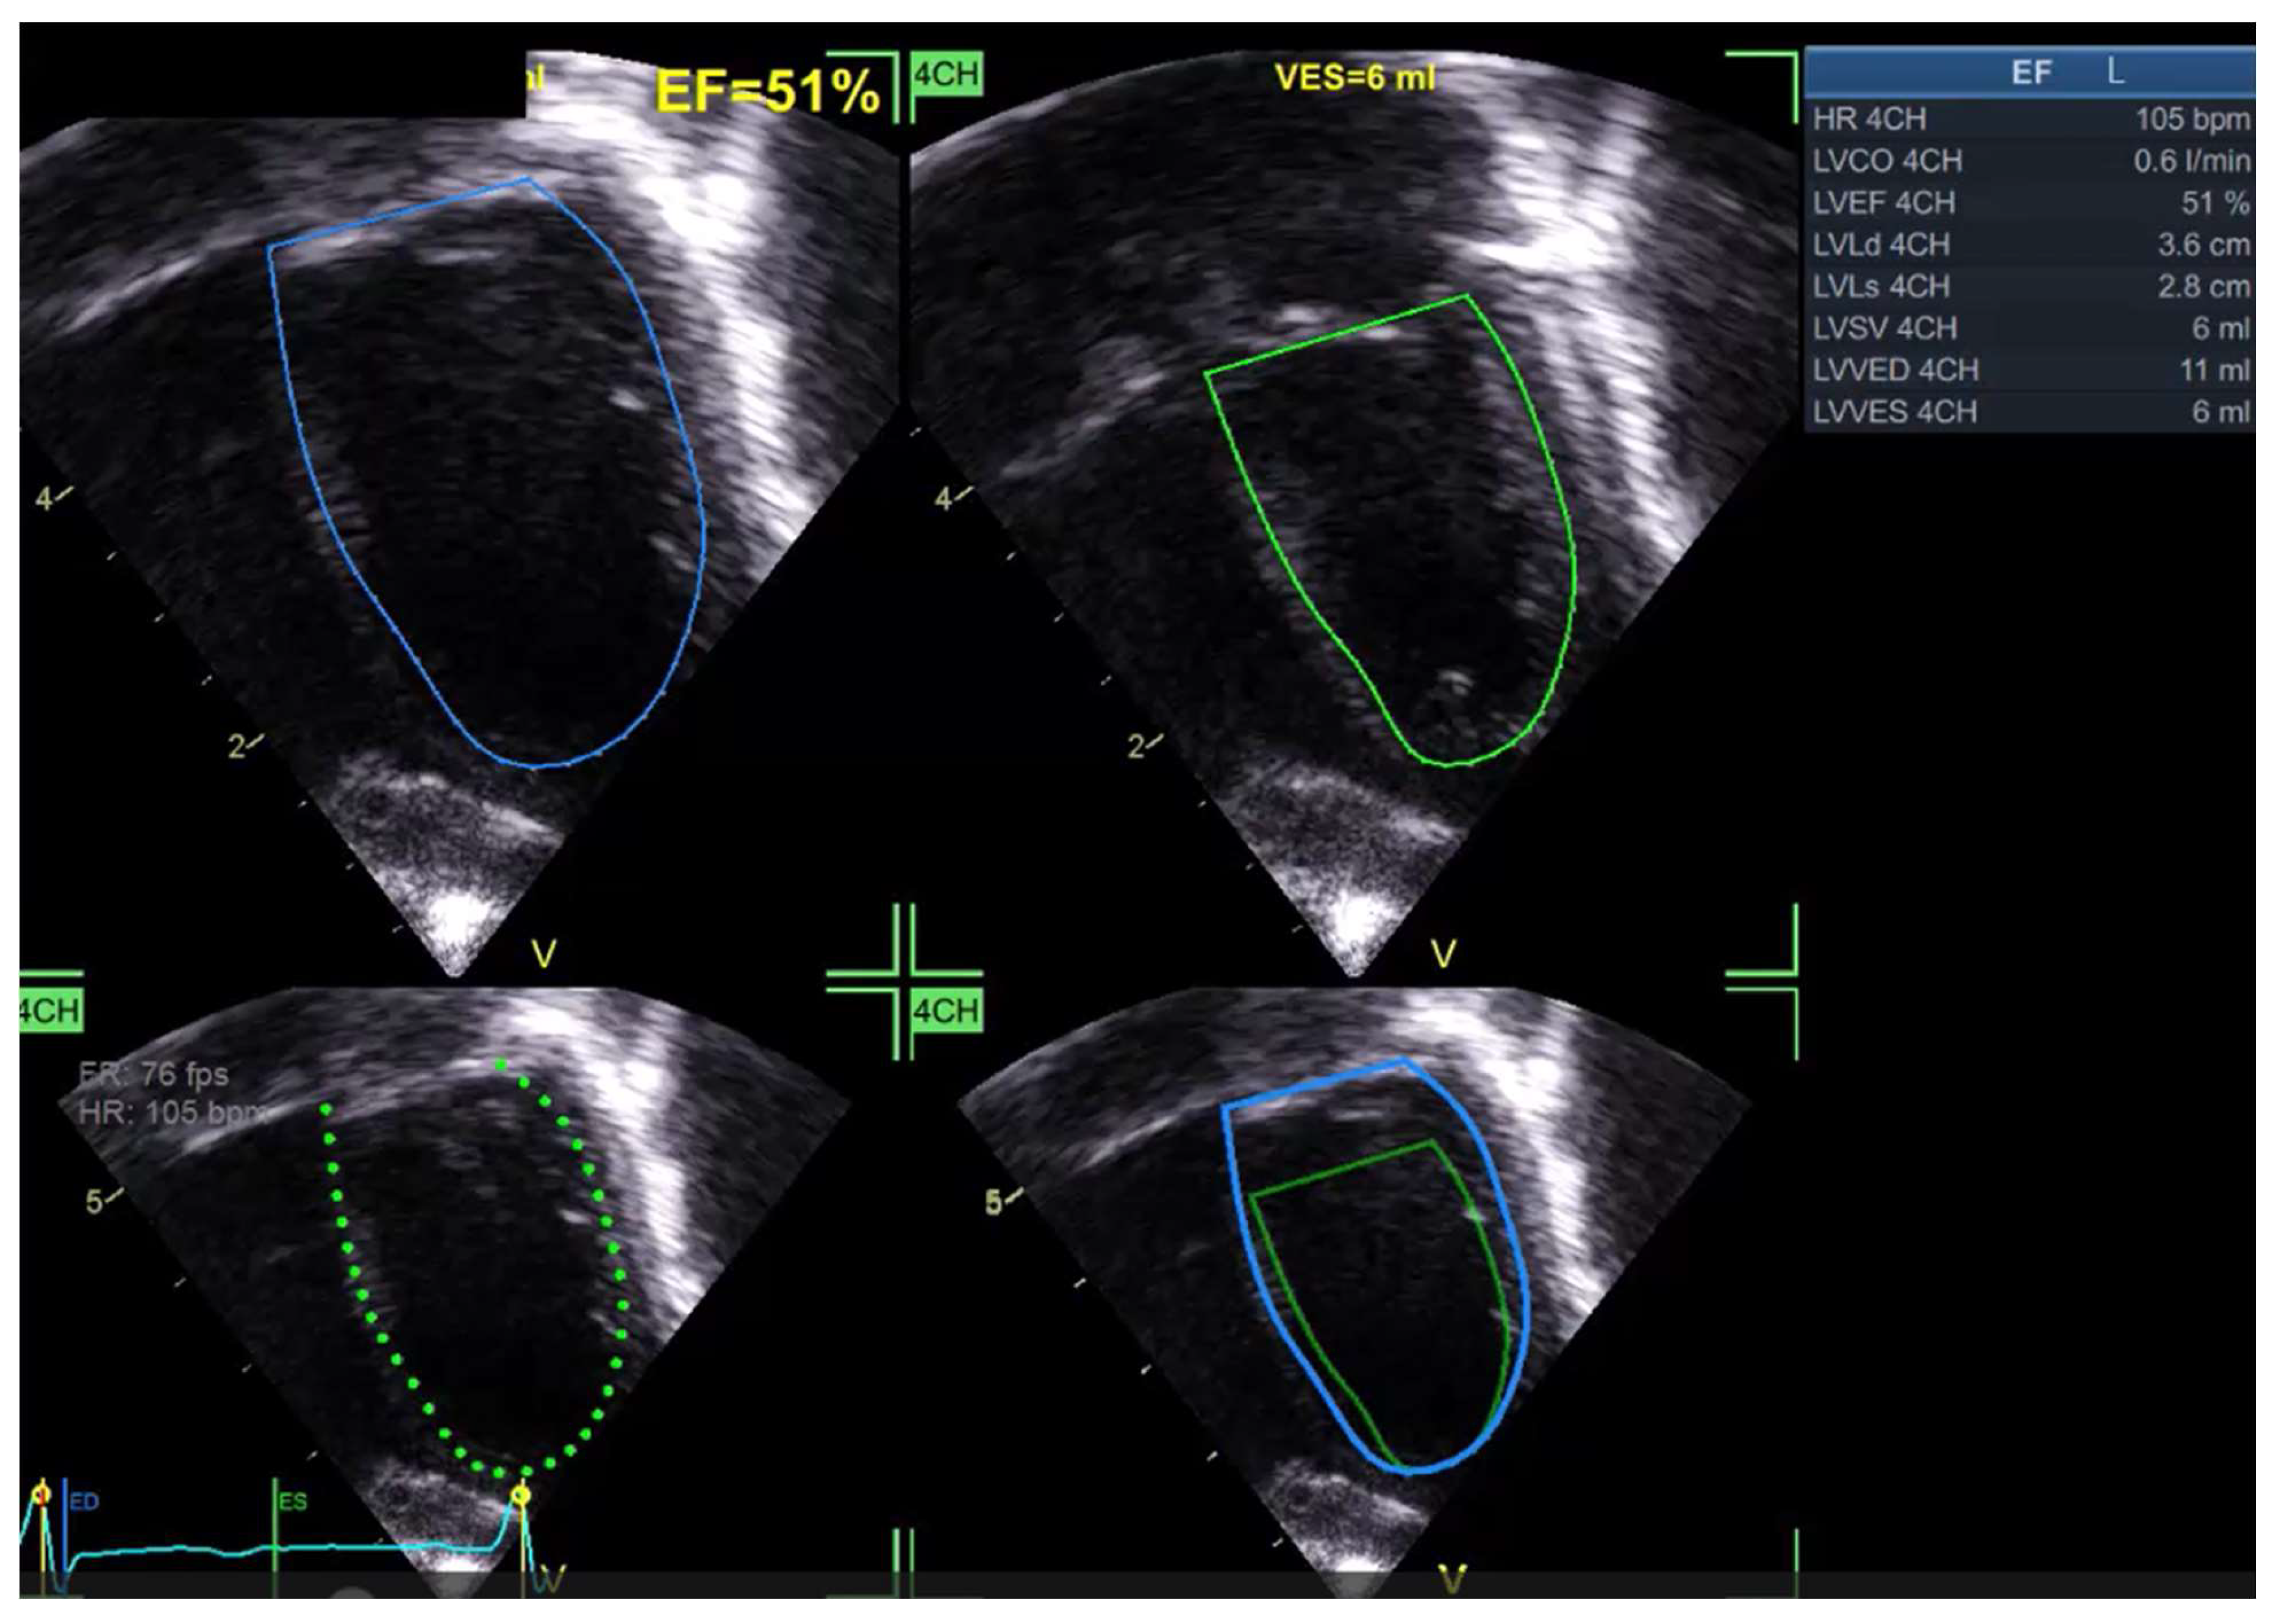

- Ahmad A, Shigemitsu S, Termachi Y, Windram J, Khoo N, Colen T, Eckersley L (2022) Comparing a knowledge-based 3D reconstruction algorithm to TomTec 3D echocardiogram algorithm in measuring left cardiac chamber volumes in the pediatric population. Echocardiography 39:1180–1189. [CrossRef]